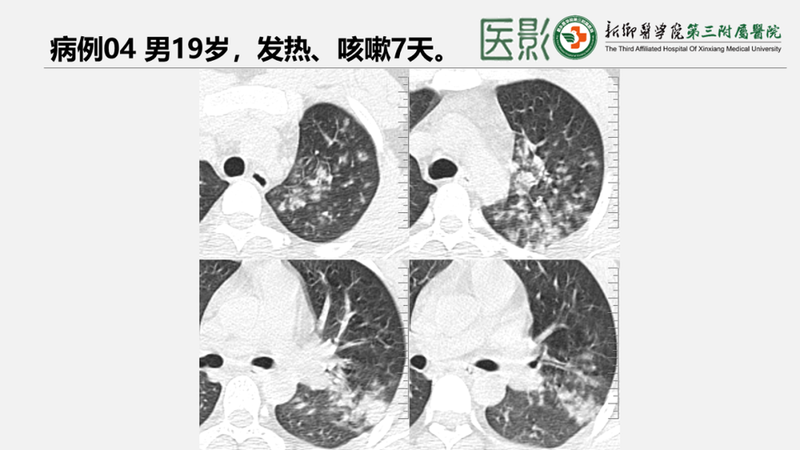

【临床】MPP潜伏期为1-3周,发病形式多样,以发热、咳嗽为主要症状。•多数仅以低热、疲乏为主,部分可出现突发高热(可>38°C)并伴有明显的头痛、肌痛及恶心等全身中毒症状。少数重症有高热及呼吸困难。发热时间可长达1-2周。•呼吸道症状以干咳最为突出,多伴有明显咽痛,偶有胸痛、痰中带血,一般咳嗽比较剧烈(干咳最为突出),咳嗽时间多为两周,而且在发热退后咳嗽还可能继续1-2周。部分可无自觉症状。5岁以下儿童患者症状多轻微。•肺外并发症——神经系统、心血管系统及肾损害持续时间较长。•实验室:外周血白细胞总数和中性粒细胞比例一般正常,少数病人可升高。支原体抗体呈阳性,发病后2-3周血冷凝集试验比值升高(可达1:64)。支原体特异性抗体lgM、lgG增高有诊断意义,但早期常阴性。